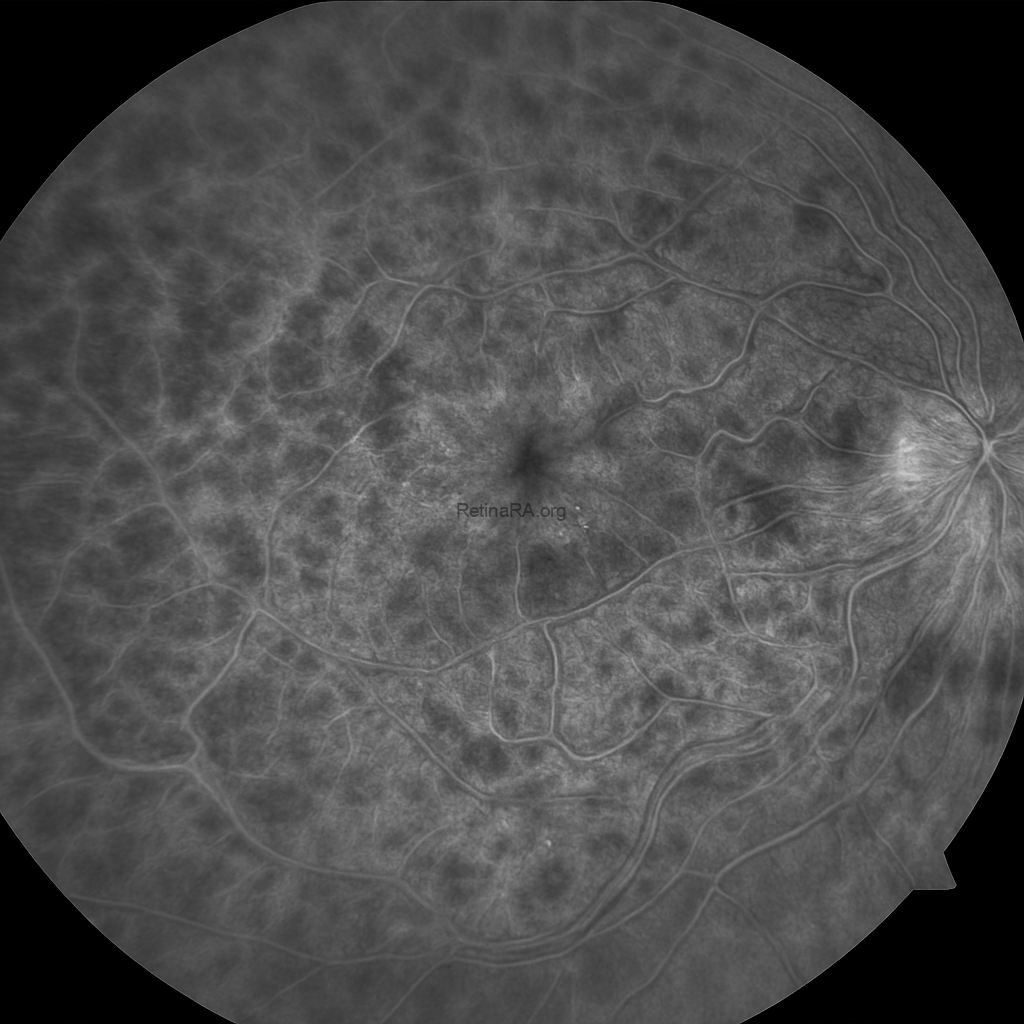

The fundus autofluorescence (FAF) image shows a heterogeneous pattern with multiple areas of hypo- and hyperautofluorescence scattered throughout the posterior pole. The dark hypoautofluorescent regions correspond to blocked signal from intraretinal hemorrhages and areas of retinal ischemia. Hyperautofluorescent spots are observed in between, reflecting metabolic stress and dysfunction of the retinal pigment epithelium (RPE). The macular region demonstrates irregular mottled autofluorescence, consistent with underlying macular edema and structural disruption. These findings are compatible with central retinal vein occlusion and highlight the extent of retinal hemorrhage and ischemia.